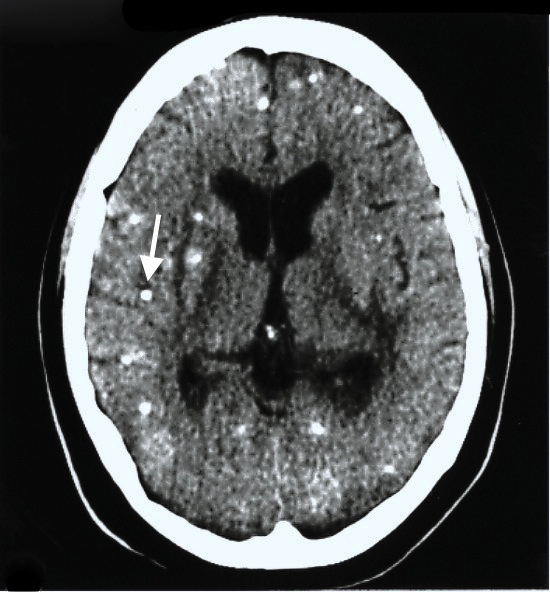

Clínica: coriorretinite, hidrocefalia, calcificações difusas no SNC

Investigação: sorologia (IgM teste do pezinho), neuroimagem, fundoscopia